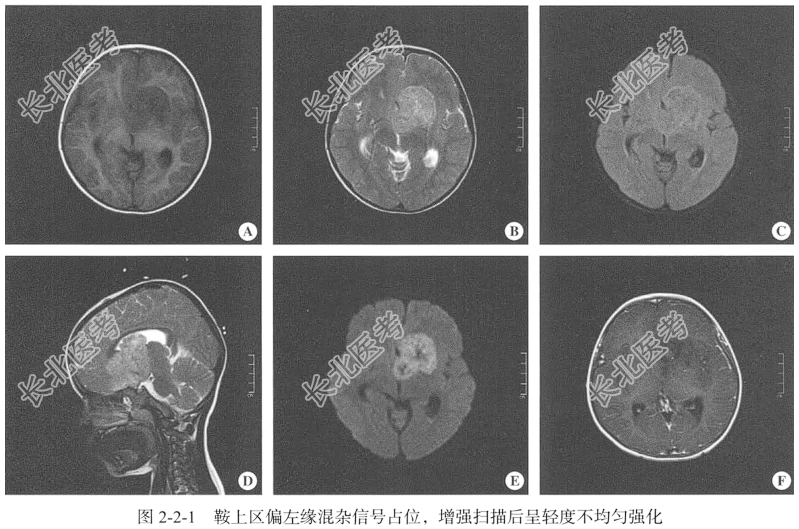

- [材料题] 【临床病史】男性,4岁8个月。头痛、呕吐2天。

【专科查体】患者神志清,精神可,定向定位准确,言语正常,查体合作,头颅无畸形,额纹对称,双侧瞳孔等大等圆,约3.0mm,光反射灵敏,闭目有力,无眼睑下垂,双侧视力粗测正常,外耳道及鼻腔无异常分泌物,双侧鼻唇沟对称,口角无歪斜,颈软、无抵抗,四肢肢体肌力5级,肌张力正常,深浅感觉正常,各生理反射存在,四肢腱反射正常,双侧病理反射阴性,脑膜刺激征阴性。

【头颅MRI检查】仰卧位,横断位扫描,包括T₁WI、T₂WI,T₂WI FLAIR,DWI扫描范围自头顶至颅底,扫描层厚为5mm,层间隔0.5mm,矩阵512×512;辅以矢状位T₂WI,平扫后行横断位的增强扫描。

【影像图片】见图2-2-1。

【手术所见】肿瘤质地稀软,血供较丰富,与周围脑组织无明显边界。

【病理所见】肉眼所见:(颅内肿物)不整组织一堆,大小为2.5cm×2.2cm×1cm,呈淡粉色、质中,镜下肿瘤实质主要由类似胚胎神经管原始未分化细胞构成,形似小圆形细胞,呈片状或巢状分布排列,胞核大,胞质少,核质比高,细胞密度高,细胞外含水少,核分裂象易见(图2-2-2)。免疫组化结果:A2:CK(-),Vim(+),GFAP(-),Olig-2(-),TdT(-),Pax5(-),CD3(-),CgA(-),Syn(+),CD56(+),Ki-67(40%+),Des(-),CD20(-),CD99(-)。

【病理诊断】幕上原始神经外胚层肿瘤(PNET),FNCLCC组织学分级:3级。